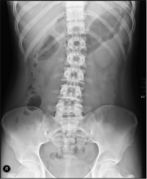

Differentiating large and small bowel

| Location | Size | Lines |

| Small bowel | 3 cm | All the way through the bowel (plica circulares) |

| Colon | 6 cm | Only halfway through the bowel (haustra) |

| Cecum | 9 cm |